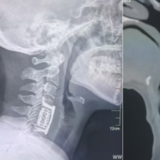

43岁的秦女士因“结肠癌术后3年,颈部及双上肢疼痛1月”入院。经影像学检查,明确诊断为结肠癌颈椎转移导致C5椎体病理性骨折,并伴有脊髓受压,如不及时手术治疗,极有可能导致高位截瘫,甚至危及生命。

经过充分的术前准备,脊柱外科手术团队历时2.5小时,顺利完成手术。术中,手术团队精准切除了受累的C5椎体,彻底解除脊髓压迫,随后植入与患者颈椎解剖结构高度匹配的3D打印人工椎体,有效重建了颈椎前柱稳定性。患者术后恢复良好,颈部及上肢疼痛显著缓解,神经功能稳定,并对脊柱外科医护团队表达了诚挚的感谢。